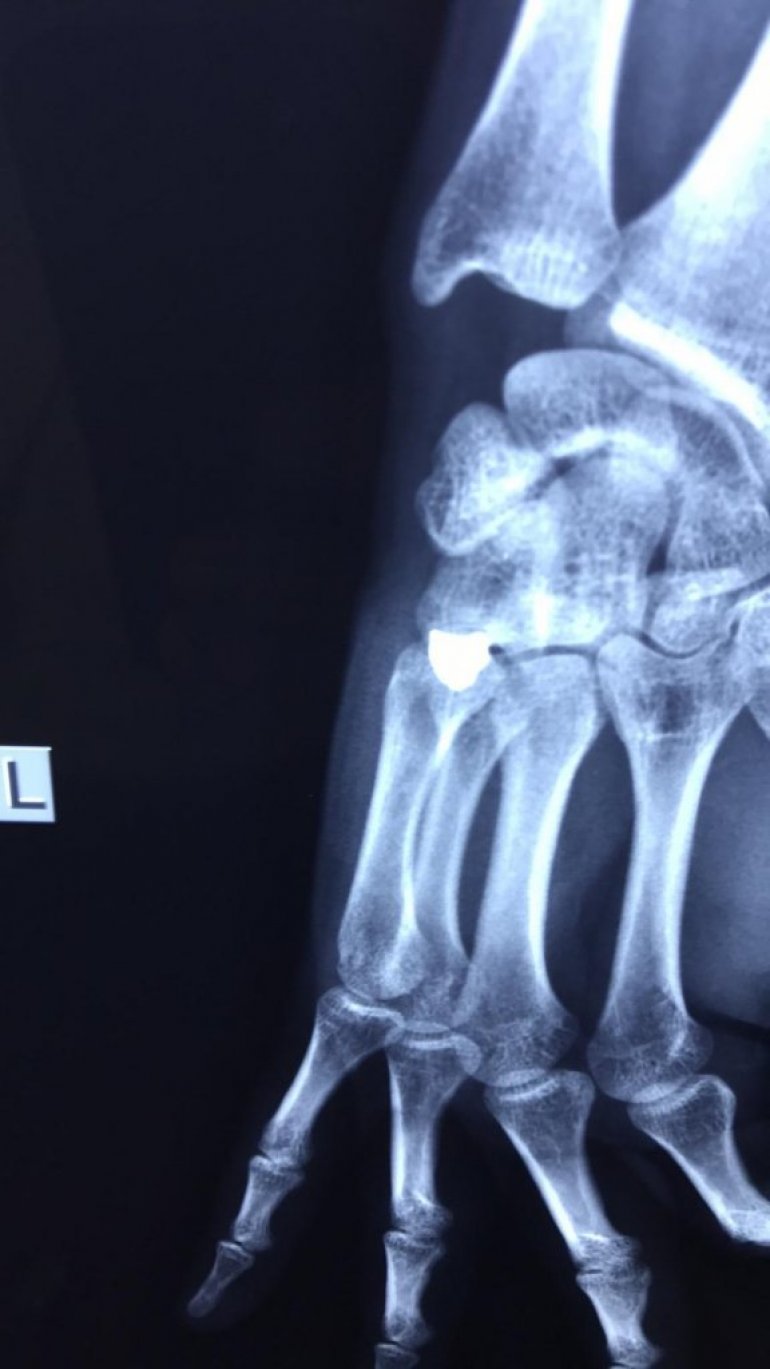

СРПСКИ дечак и његов рођак Стефан С. (11) и Милош С. (21) рањени су данас у Готовуши код Штрпца када је на њих, без икаквог повода, из возила у покрету пуцао локални Албанац, саопштила је Канцеларија за Косово и Метохију.

Хируг Божидар Одаловић у Грачаници, казао је да су Милош и Стефан Стојановић ван животне опасности, након извршене хирушке интервенције.

Погледајте и фотографије рентгентског снимка повређеног младића и фотографију метка којим је рањен Милош.